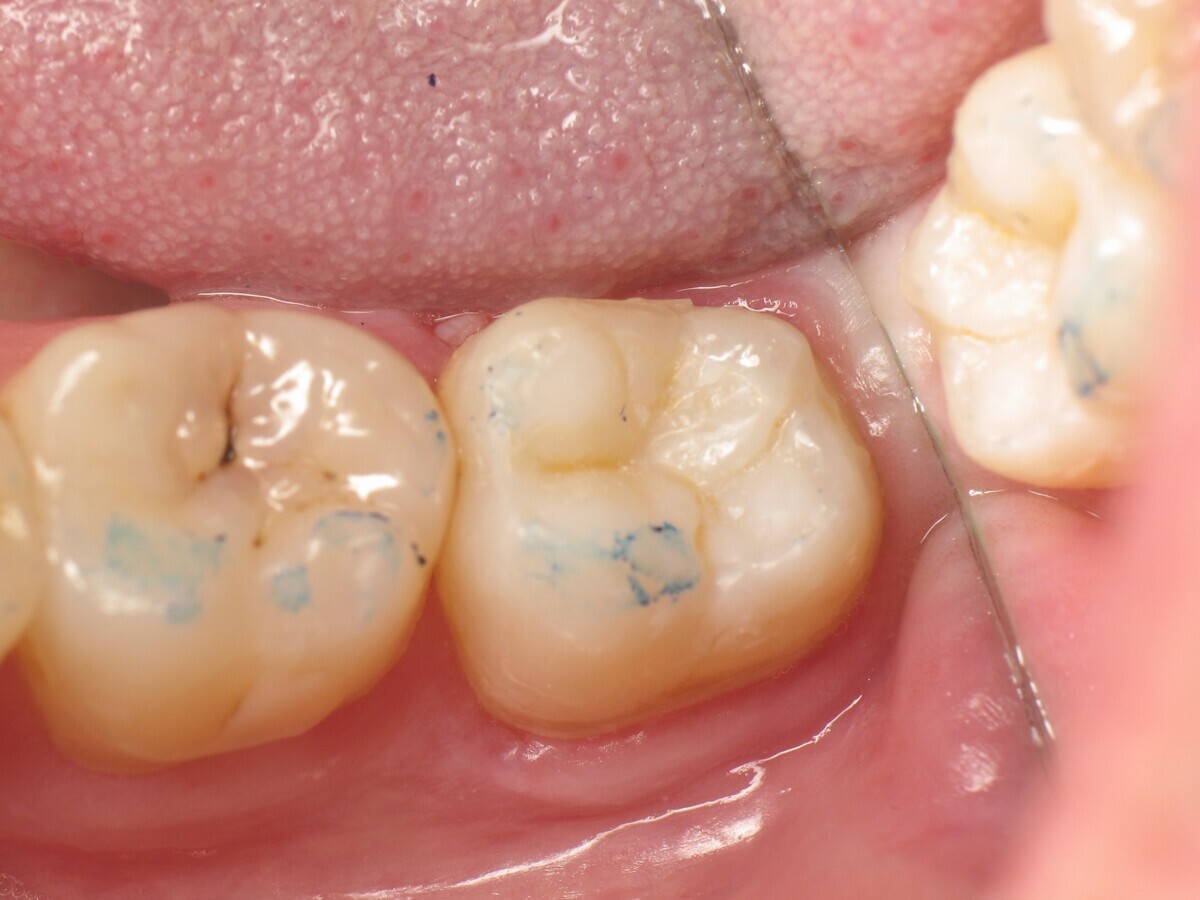

La secuencia fotográfica muestra la cavidad después de la aplicación y fotopolimerización del adhesivo y el modelado que se obtiene con el composite termoviscoso. Fotos: Yassine HARICHANE

Este artículo describe el tratamiento de una cavidad clase I en un molar utilizando un composite termoviscoso mediante la técnica de la almohadilla (Figura 1). En primer lugar, se registran los detalles anatómicos utilizando una resina transparente, fluida y fotopolimerizable (Clip Flow, VOCO). El diente se aísla con un dique antes de aplicar el composite transparente a la superficie oclusal con un cepillo aplicador y fotopolimerizar durante 10 segundos (Figuras 2-4). La almohadilla oclusal así obtenida (Figura 5) debe almacenarse en alcohol (etanol o isopropanol) para eliminar la capa de inhibición. Luego se limpia la cavidad clase I (Figuras 6 y 7). A continuación se graba el esmalte durante 30 segundos y la dentina durante 15 segundos (Conditioner 36, Dentsply Sirona) y luego se enjuaga bien (Figuras 8 a 10). Debido al bajo espesor de la dentina remanente, también se aplica protección pulpar (Telio Desensitizer, Ivoclar Vivadent) (Figura 11). Luego se frota el adhesivo sobre las superficies dentales durante 20 segundos (Futurabond DC, VOCO), luego se seca bajo una pulverización de aire sin aceite graso durante 5 segundos y luego se fotopolimeriza durante 10 segundos (Figuras 12, 13). Para una humectación óptima, el fondo de la cavidad se cubre con un compuesto fluido de baja viscosidad (GrandioSO Light Flow, A3.5, VOCO) y se fotopolimeriza durante 20 segundos (Figuras 14, 15). Utilizando el Dispensador VisCalor, un dispensador portátil que permite el calentamiento y la aplicación simultánea de resinas, la cavidad se llena luego con un composite termoviscoso bulk (VisCalor Bulk, A2, VOCO).

El composite calentado tiene una consistencia fluida para un perfecto manejo y se puede aplicar en capas de hasta 4 mm (Figura 16). A medida que se enfría hasta la temperatura corporal, la viscosidad del composite termoviscoso aumenta, lo que lo hace muy fácil de modelar (Figura 17). Finalmente, se realiza la fotopolimerización durante 20 segundos (potencia ≥ 1.000 mW/cm2, Figura 18). El uso de un composite bulk permite un llenado rápido en un solo paso. Si se requiere una segunda capa, la capa superior también se puede realizar con composite termoviscoso estético universal VisCalor en color A1 (VisCalor, VOCO, Figura 19), que se fotopolimeriza en incrementos de 2 mm. La consistencia innovadora del composite termoviscoso permite una reproducción fácil de la anatomía y una eliminación fácil del exceso de material (Figura 20) [Ilie et al. 2014]. A continuación se aplica la almohadilla oclusal creada previamente (Figura 21). La fotopolimerización se realiza primero con la almohadilla y luego sin durante 20 segundos cada una (Figuras 22 a 24). No se requiere material separador entre el material compuesto y la almohadilla. Debido a la eliminación previa de la capa de inhibición de la almohadilla, hay muy pocos o ningún punto de contacto, de modo que no se puede crear ningún enlace químico real entre la almohadilla y la resina. Los pocos puntos de contacto presentes solo significan que puede sentir una ligera resistencia cuando se retira la almohadilla después del primer ciclo de fotopolimerización.

El resultado final es muy natural y reproduce fielmente la anatomía de la superficie oclusal en el estado preoperatorio (Figura 30).

Figura 30. Control de oclusión.